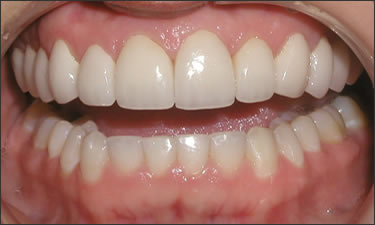

This young patient was self-conscious about the appearance of her short teeth and gummy smile. Through crown lengthening and tooth whitening procedures, we were able to create a beautiful, more mature smile.

Click on a thumbnail to view the before and after photos.